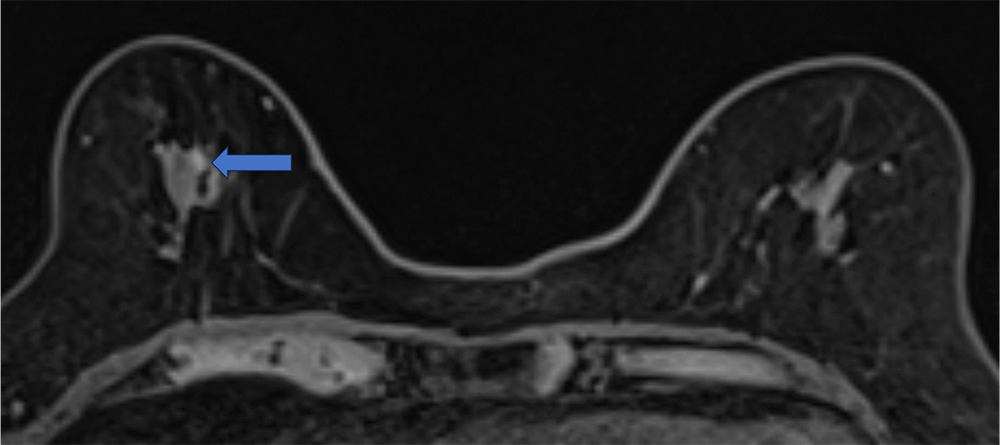

4. ダイナミックMRI 造影前 早期相 遅延相

病変は扁平な形状で均一に増強される。ダイナミックMRIの増強パターンはfast and plateauであった。

ダイナミックMRI 早期相

ダイナミックMRI 遅延相